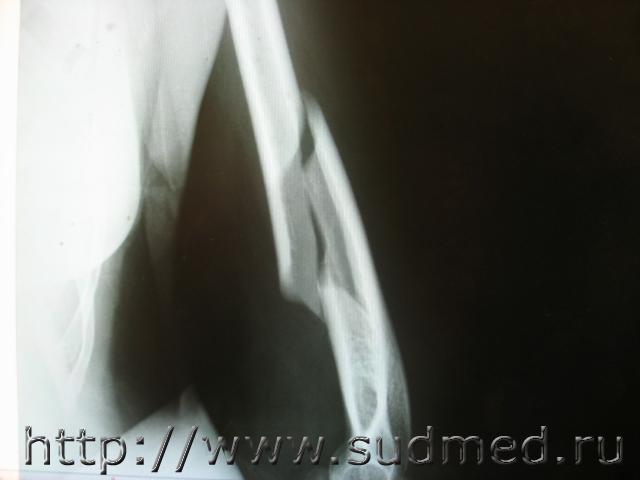

Нужна помощь в определении механизма перелома.

Экспертиза живого лица, дополнительная. Вопрос эксперту: возможность причинения перелома при падении из вертикального положения. Показания:

Проект выводов: 1. Винтообразная форма линии перелома - деформация кручения плеча вокруг своей оси, возможно при обстоятельствах указанных потерпевшим. Причинение перелома при падении из вертикального положения не характерно, в том числе при обстоятельствах, отраженных в протоколе следственного эксперимента.

Фото рентгенограмм прилагаю.

1. Винтообразный перелом плеча как раз характерен для падения из вертикального положения с упором на ладонь выпрямленной руки. Без этих дух условий - упор на ладонь с осевой нагрузнкой на плечо и выпрямленная рука, образование винтообразного перелома невозможно.

2. Судя по приведенной фотографии оба ключевых момента отсутствуют, что позволяет категорически исключить возможность образование винтообразного перелома при таком падении.

3. Образование такого перелома возможно, в том числе и при ударе по лотевому суставу или нижней трети плеча заведенной за спину руки - при этом заведение руки за спину создает вращательно сдвиговые напряжения в плечевой кости, а дополнительное поперечное воздействие в область перелома или вблизи него, выполняет роль дополнительного нагружения, после которого и может образоваться винтообразный перелом.

Я бы дал название перелому: винтообразно сгибательный (зубовидный край отломка) (диссертации после 2000 года Кислова М., Леоновой Е.).

Топики иногда читают и после закрытия обсуждения. На снимке реально очень красивый перелом, вот я и решил внести свою лепту.